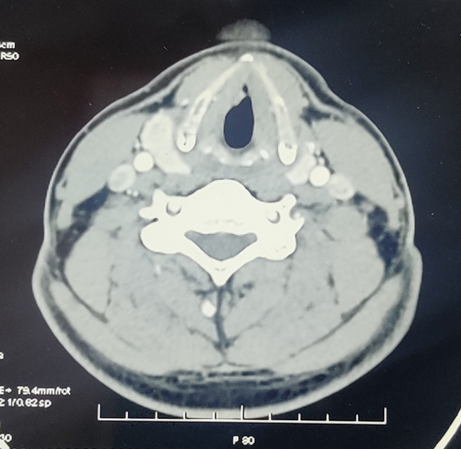

On examination he was sitting well with normal blood pressure. His SpO2 was 99% without any support. Oral cavity examination was normal. Rigid laryngocopy revealed a papillomatous pinkish swelling presented over anterior 2/3rd surface of right true vocal fold. This lesion reaches till anterior commissure and involving the anterior 1/3rd aspect of left true vocal fold.(Figure 1A-C) Both the true vocal folds were mobile with normal rest of the anatomical subsites. Patient underwent for computed tomography (CT) scan and it was reported as 8.3 x 8.8 x 7.1 mm nodular mildly enhancing soft tissue noted at anterior part of the right true vocal cord. (Figure 2) The patient was scheduled for microlaryngeal surgery under general anaesthesia.

Figure 2 CT scan: 8.3 x 8.8 x 7.1 mm nodular mildly enhancing soft tissue noted at anterior part of the right true vocal cord.